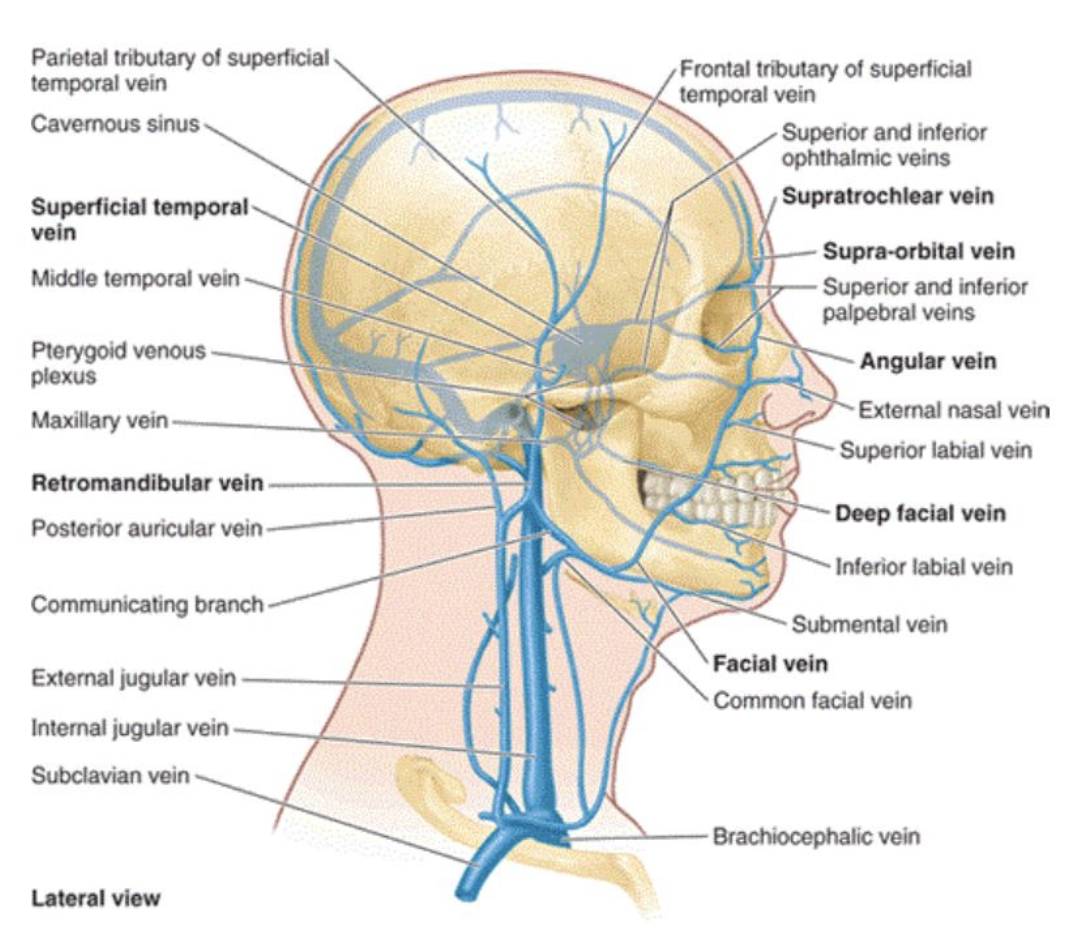

Vein

顱內

- Superficial temporal:

- Anterior to the Superficial temporal a.

- Joins the maxillary v. to form the

- retromandibular v.